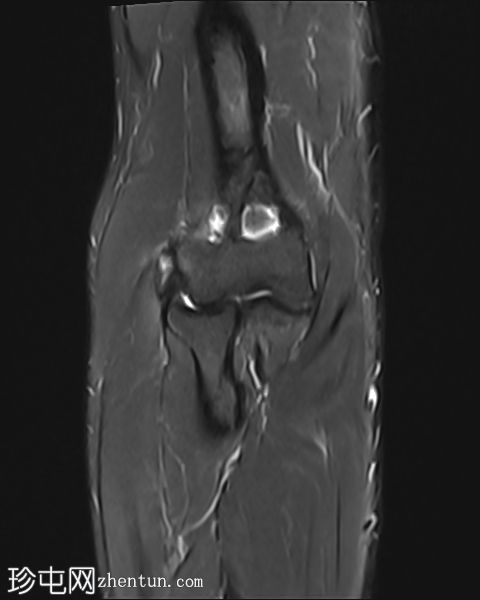

MRI

冠状位

T1加权像

STIR序列

轴位

T2加权像

梯度回波序列

肘关节伸肌总腱增厚,腱内可见高信号及部分撕裂。伴周围软组织水肿。

病例讨论

本病例展现了网球肘的典型

影像

学特征。